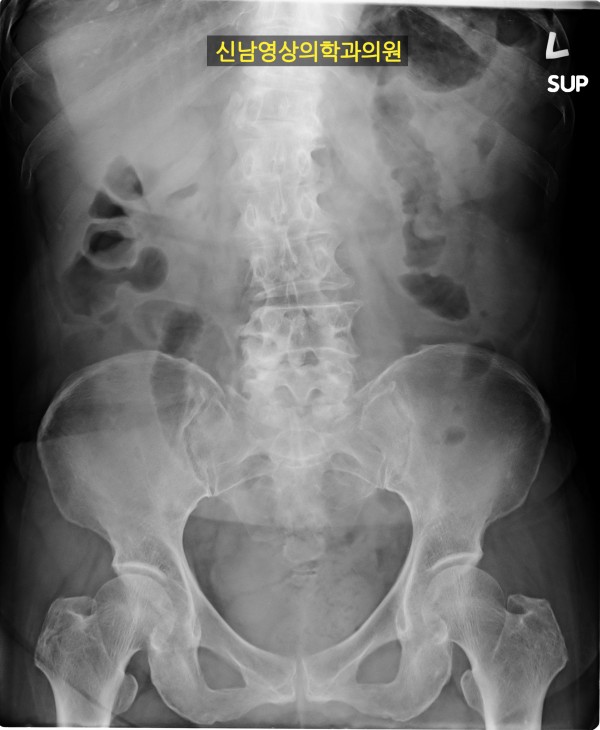

본 환자분께서는 사흘 정도 지속되는 복통과 고열로 내원하신 60대 중반의 환자분입니다.

복통 부위의 병변을 확인하기 위해서 복부 촬영과 복부 초음파검사를 진행했고, 맹장은 이상이 없고, 대장 주위로 복강삼출액(물)이 둘러싸고 있으면서 상행대장부위의 부종이 심하게 발견되었습니다.

원내 피검사상 백혈구 수치가 높아 대학병원 응급실로 전원 조치하고 응급수술을 받으셨고...

1년 뒤 수술 부위에 탈장이 발생하셔서 탈장 수술을 받으셨던 분입니다.